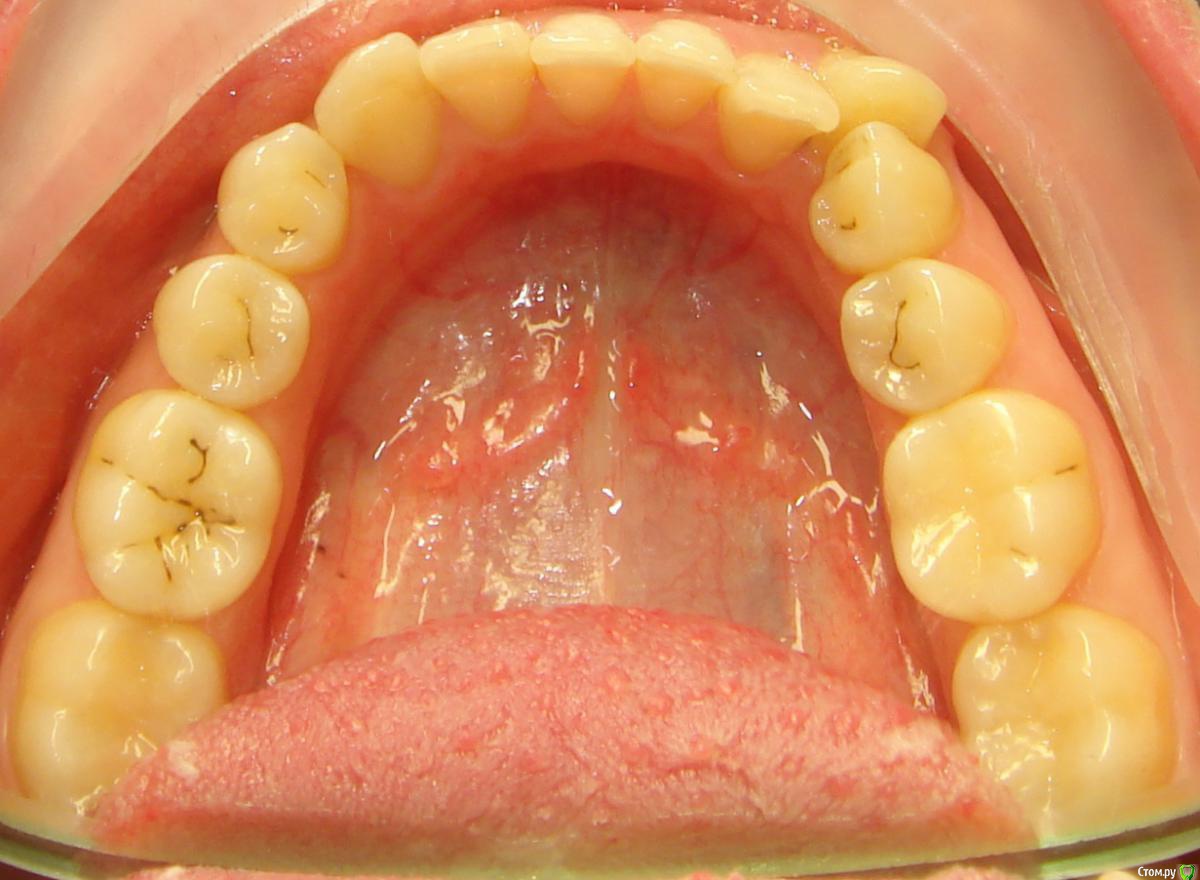

Opdihatop Опубликовано 10 декабря, 2016 Поделиться Опубликовано 10 декабря, 2016 Добрый вечер, коллеги! У меня вопрос к тем, у кого опыта по MEAW больше, чем у меня. Пациентка, 24 года, на данный момент все зубы мудрости удалены, привычная окклюзия по резцам - край в край. Сам процесс я понимаю, но есть несколько нюансов, которые хотелось бы уточнить:1) Нивелировать ли просто фронт в/ч, как книжка пишет (просто поставить дугу и все), или все-таки немного дистализировать боковые участки? С одной стороны простое нивелирование ускорит процесс и облегчит перебрасывание резцов, с другой стороны я опасаюсь чрезмерной протрузии из-за выравнивания дистопированных клыков; но при этом дистализация усугубит 3-й класс.2)Какой высоты делать окклюзионные накладки, в книжке они минимальные, а мне как то хочется побольше, чтобы резцы разомкнуть почти край в край, но не испортит ли это биомеханику?Буду очень благодарен вам за помощь! Ссылка на комментарий